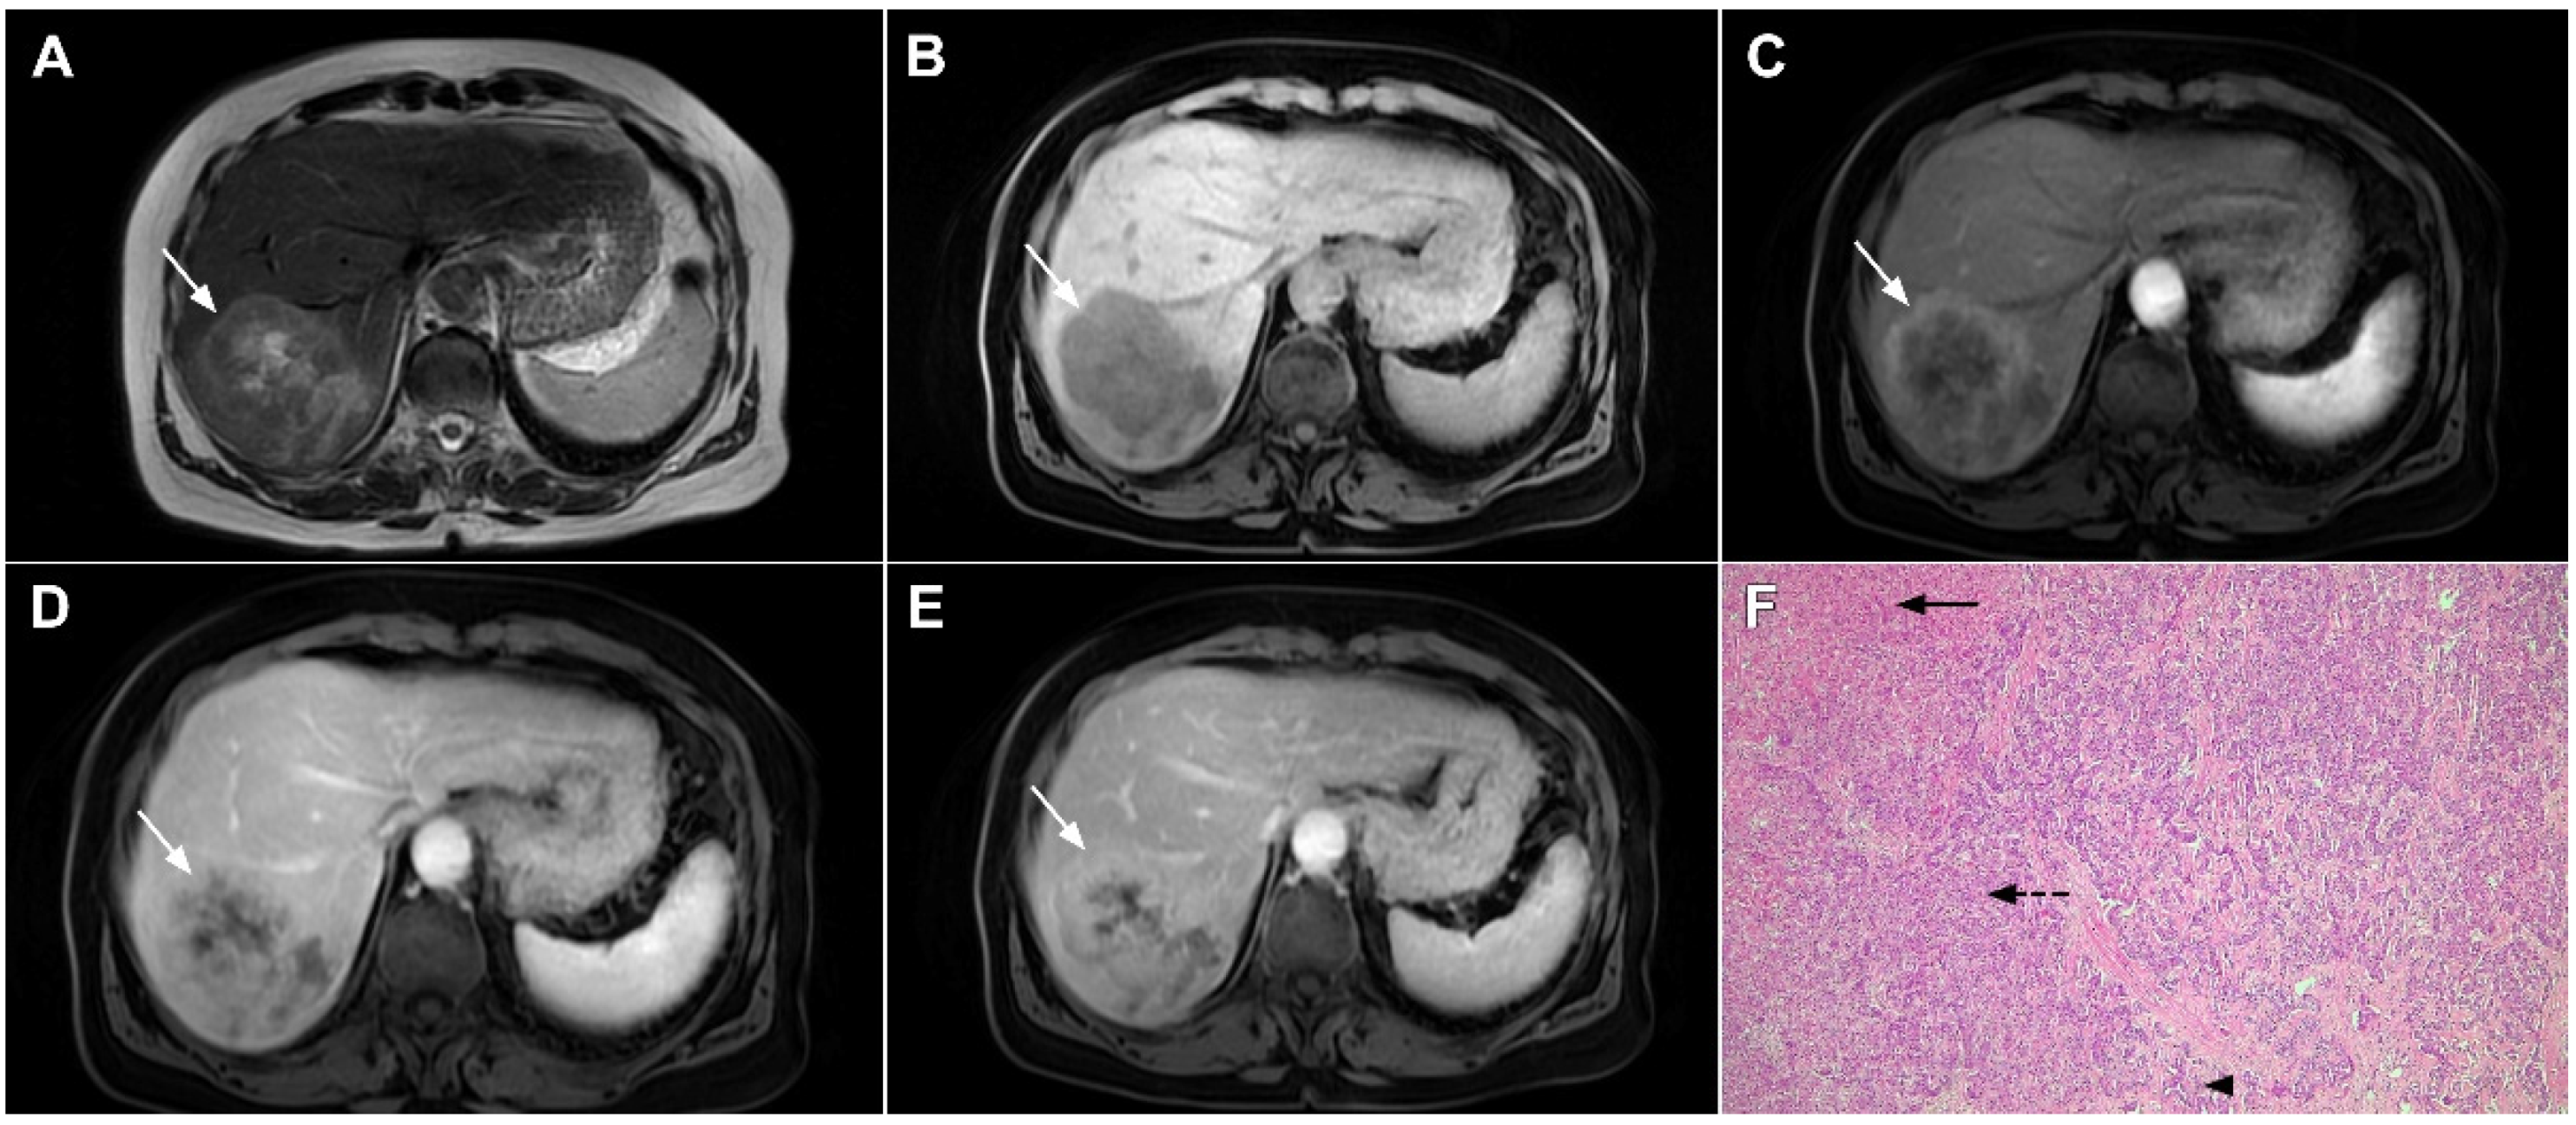

Figure 17.

Scirrhous hepatocellular carcinoma in a 68-year-old woman. The axial T2-weighted image (A) shows a moderately hyperintense subcapsular-located lesion in liver segments VI and V (arrow). Note also the capsular retraction. The tumor (arrow) is hypointense in the plain T1-weighted FS image (B), with ring enhancement in the arterial phase (C) and slight progressive central enhancement in the portal venous (D) and delayed phases (E). Hematoxylin and eosin (H&E) staining showed hepatocellular carcinoma (arrow) and normal liver parenchyma adjacent to the tumor (dashed arrow); original magnification ×40 (F).